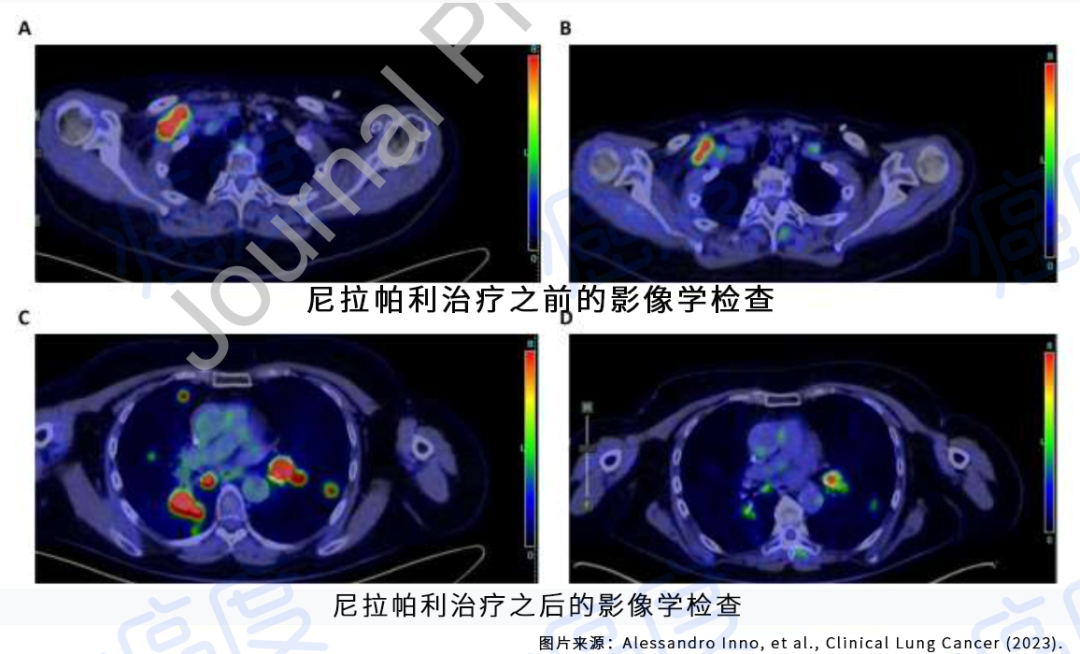

歪打正着?卵巢癌靶药尼拉帕利治疗肺癌,肿瘤病灶大幅度缩小!...

歪打正着?卵巢癌靶药尼拉帕利治疗肺癌,肿瘤病灶大幅度缩小!...